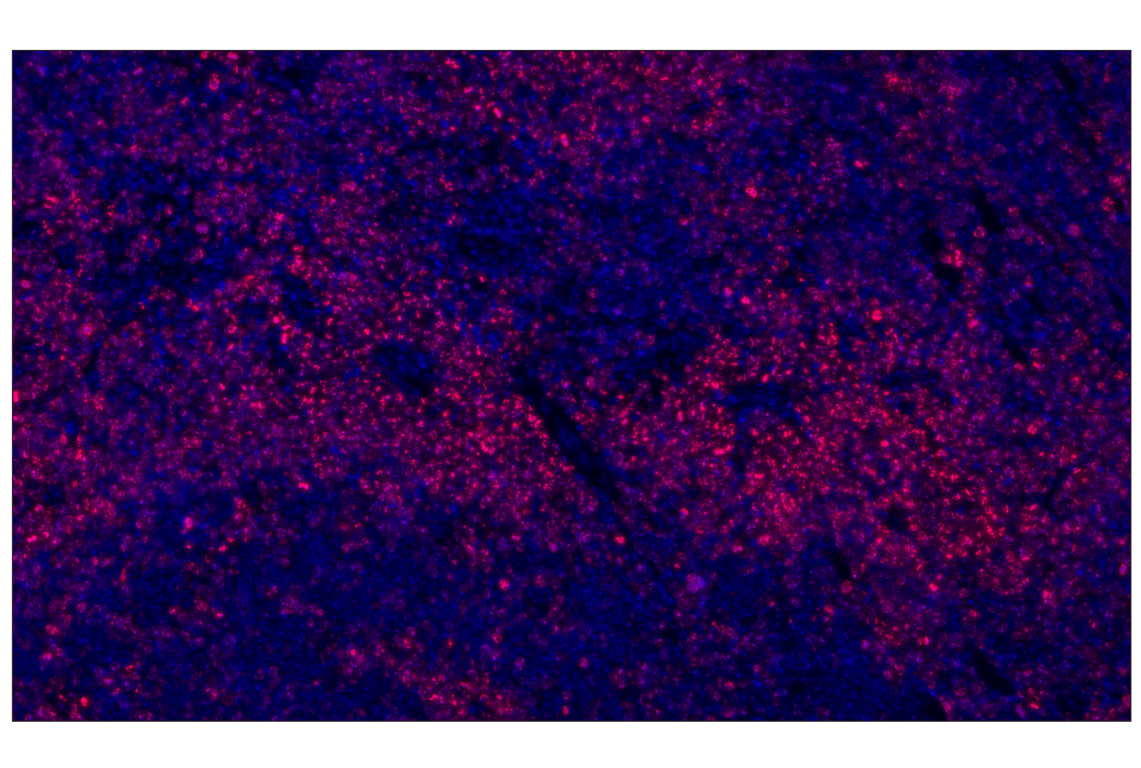

Ki-67 (D3B5) Rabbit Monoclonal Antibody (Alexa Fluor® 555 Conjugate) #31702

This Cell Signaling Technology® antibody is conjugated to Alexa Fluor® 555 fluorescent dye under optimal conditions. This antibody conjugate is expected to exhibit the same species cross-reactivity as the unconjugated Ki-67 (D3B5) Rabbit mAb #12202.

Ki-67 (D3B5) Rabbit Monoclonal Antibody (Alexa Fluor® 555 Conjugate) recognizes endogenous levels of murine Ki-67 protein. This antibody conjugate will also detect endogenous levels of human Ki-67 protein; however, Ki-67 (D2H10) Rabbit Monoclonal Antibody #9027 is recommended for the detection of human Ki-67 protein in paraffin-embedded tissues.

Monoclonal antibody is produced by immunizing animals with a recombinant protein fragment corresponding to residues near the central region of human Ki-67 protein.

Ki-67, named after the location where it was discovered (Kiel University, Germany), is a nuclear nonhistone protein (1) that is universally expressed among proliferating cells and absent in quiescent cells (2). Ki-67 detects proliferating cells in G1, S, G2, and mitosis, but not in the G0 resting phase. Research studies have shown that high levels of Ki-67 are associated with poorer breast cancer survival (3). Research studies have explored the use of Ki-67, along with other markers, as potential prognostic or predictive markers in breast cancer and other malignant diseases (4).